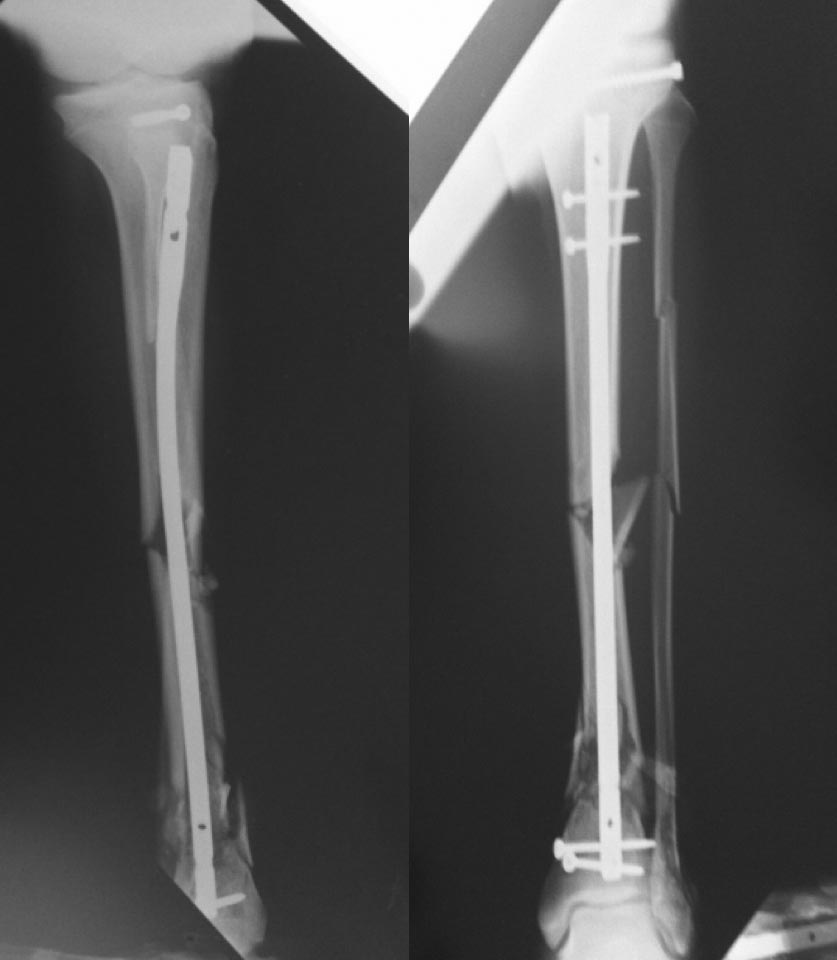

Снимки от мая 2016

В раннем п/о периоде